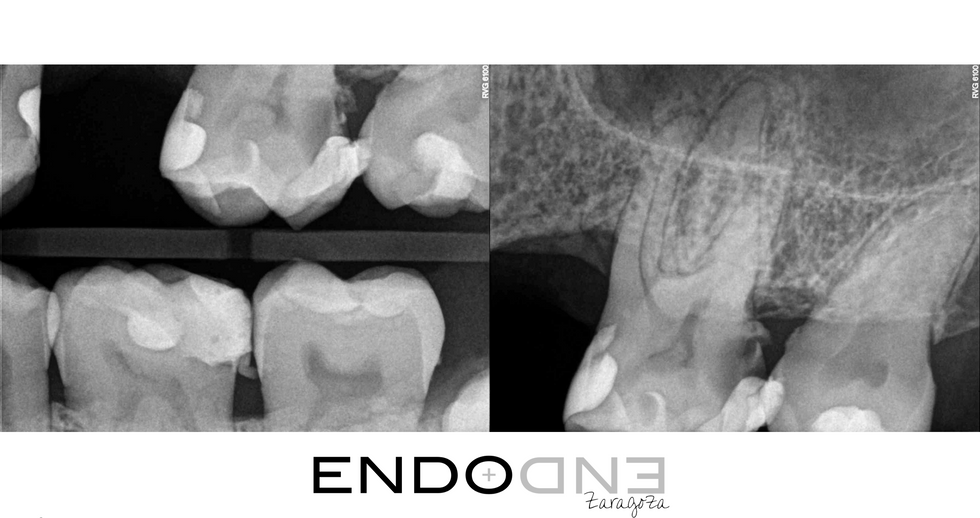

Cuando hay una caries distal subgingival, la mejor alternativa siempre antes de realizar la endodoncia es limpiar la zona afectada y restaurar la pieza.

En esta ocasión el paciente presentaba molestias intensas con el frío, y también percusión positiva. El diagnóstico fue de pulpitis irreversible pero, como se puede apreciar claramente en la imagen, había diferente estado pulpar en las distintas raíces. Mientras que la raíz distovestibular presentaba necrosis pulpar, las mesiovestibular y palatina mostraban un sangrado profuso, característico de una inflamación inrreversible.

Siempre que iniciamos el tratamiento de endodoncia en un primer molar superior, debemos tener presente que es muy probable que exista un cuarto conducto. En esta ocasión, tras explorar cuidadosamente la cámara pulpar no se veían rastros de su existencia pero al emplear la magnificación del microscopio dental, observamos un pequeño surco que nacía del conducto MV. Tras explorarlo con puntas ultrsónicas finas, localizamos allí la entrada del conducto mesiopalatino. A pesar de su cercanía con el mesiovestibular, como podemos observar en las radiografías finales, tiene un recorrido totalmente independiente.